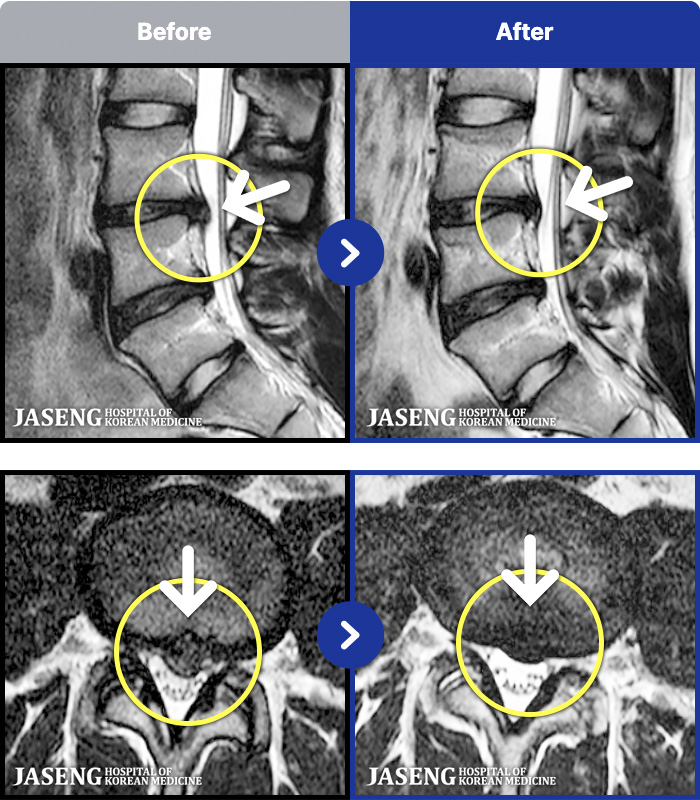

ȯںп Ǹ ǿ ԿǾ, ο ġ ۿ Ƿ ġḦ Ͻñ ٶϴ.